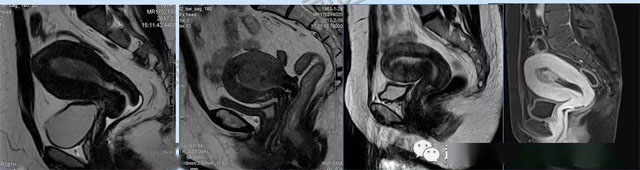

婦科疾病常常讓女性陷入了焦慮。主要是這類疾病婦女有難言之隱,癥狀隱匿,病情復雜。磁共振體檢車的金光火眼能力可以破解各種婦科難題。哪些情況需要使用磁共振檢查,檢查過程是否有不適。這些都是可以解決的。例如子宮常見疾病的磁共振診斷。

磁共振VS傳統(tǒng)檢查:有這些優(yōu)勢?無輻射安全系數(shù)高,磁共振沒有電離輻射,適合備孕跟孕婦檢查。它對軟組織有高清的成像效果,可以清晰的看到子宮各層的結(jié)構??梢宰R別細小的肌瘤,早期的癌癥腫瘤??梢园l(fā)現(xiàn)其他設備難以檢查到的深部子宮內(nèi)膜異位結(jié)節(jié)。多序列成像和增強掃描檢查,判斷腫瘤的良性準確率高達90%以上。